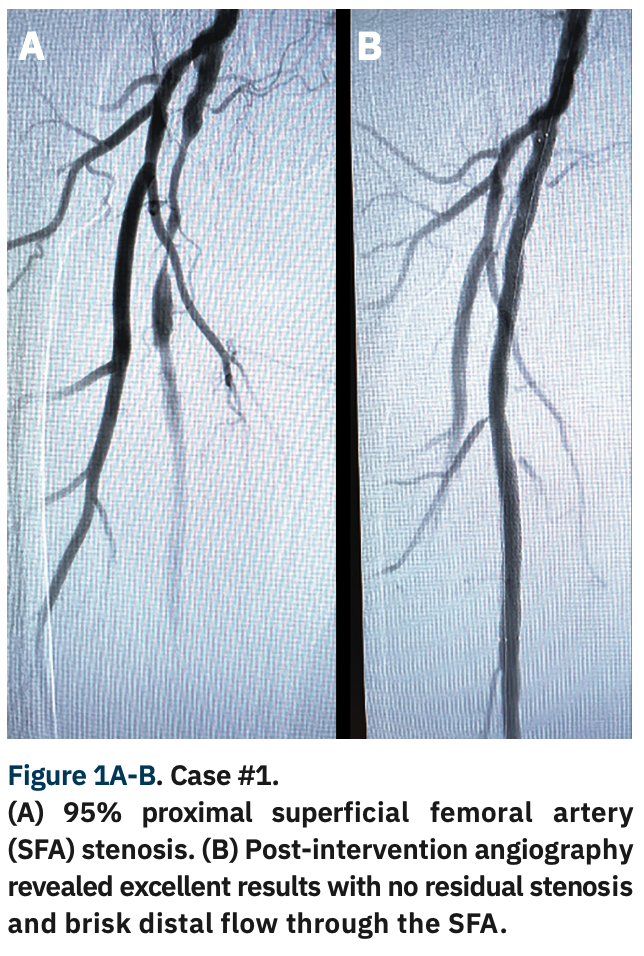

Given the shortage of time slots due to staffing issues during the COVID pandemic, we elected to proceed with the right lower extremity angiography instead of finding another peripheral cath lab schedule opening. A 5 Fr pigtail was advanced to the distal aorta and angiography demonstrated a 95% proximal SFA stenosis (Figure 1A). We decided to exchange the 5 Fr radial sheath with a 6 Fr, 119 cm R2P DESTINATION SLENDER, advanced over an .035-inch GLIDEWIRE ADVANTAGE® to the right common femoral artery. An .018-inch GLIDEWIRE ADVANTAGE TRACK™ Guidewire (Terumo) was successfully advanced across the lesion and a 6 mm x 120 mm R2P METACROSS Balloon was used to predilate the lesion. A 7 mm x 150 mm R2P MISAGO RX Self-Expanding Peripheral Stent was advanced over the wire and deployed at the lesion. Post dilation was performed with the same balloon.

Post-intervention angiography revealed excellent results with no residual stenosis and brisk distal flow through the SFA (Figure 1B). The sheath was removed and a TR Band® (Terumo) was applied. The patient tolerated the procedure extremely well. The total added time was about 10 minutes and the patient was able to be discharged home in two hours. Radial access allowed us the flexibility of using the same access site for angiography of both the coronary and peripheral arteries, as well as peripheral intervention. The use of radial access also permitted rapid, safe discharge with a low risk of bleeding and complications.